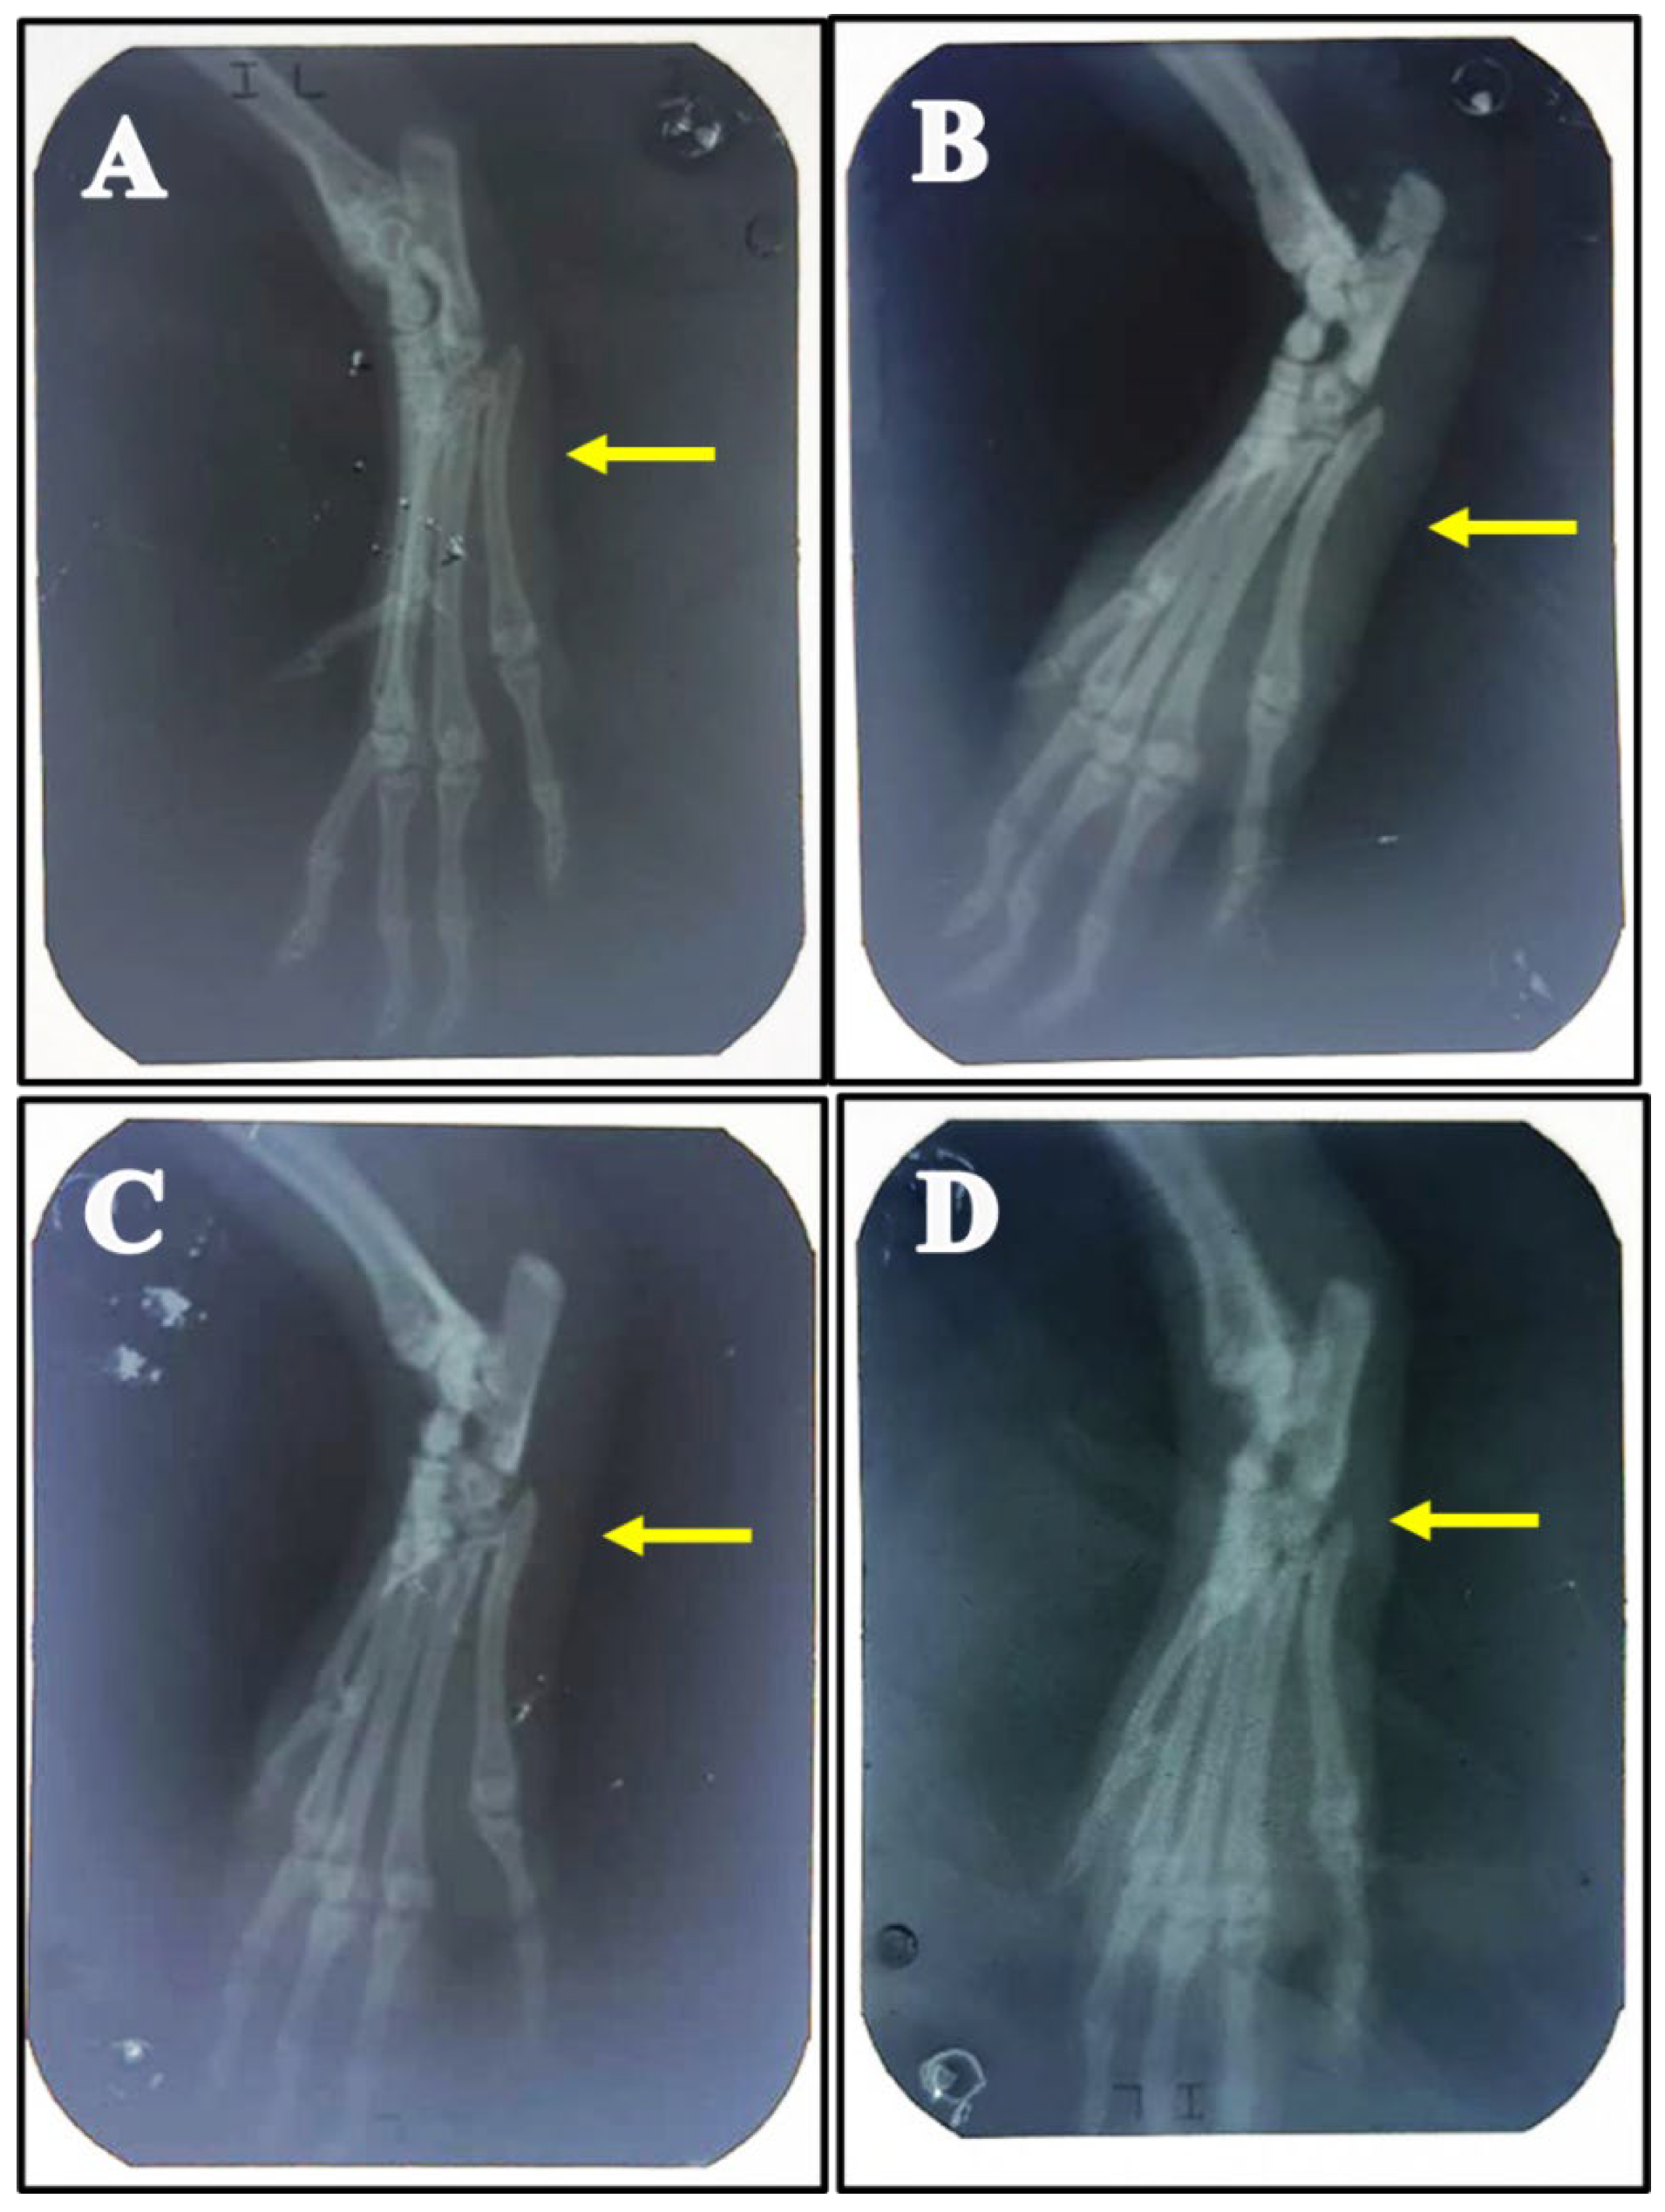

As shown in (Figure 1) MSU injection in the ankle joint produced knee joint swelling at different times (2, 4, 8, 12, 24, and 48 h) by 45%,60%,75%,80%,55%, and 35% respectively with maximum swelling at 12 h after injection which gradually subsides with time and markedly decreased at 48 h. This swelling was markedly decreased (p < 0.001) by pretreatment with Stevia extract and single Colchicine treatment compared with the MSU-group. This effect was confirmed by X-ray photographing of the ankle joint before scarification as there was mild swelling of soft tissue in the MSU-group, while Stevia and Colchicine groups showed near-normal soft tissue as presented in Figure 2.

Figure 2.

Therapeutic effects of Stevia on swollen paw rats with monosodium urate-induced gouty arthritis. (A) Representative X-ray picture of rat hind paws before scarification shows normal soft tissue in control rats. (B) Mild paw swelling was seen in monosodium urate-induced gouty arthritis. (C,D) Near-normal soft tissue was observed in rats treated with Stevia 250 mg/kg and colchicine groups respectively.